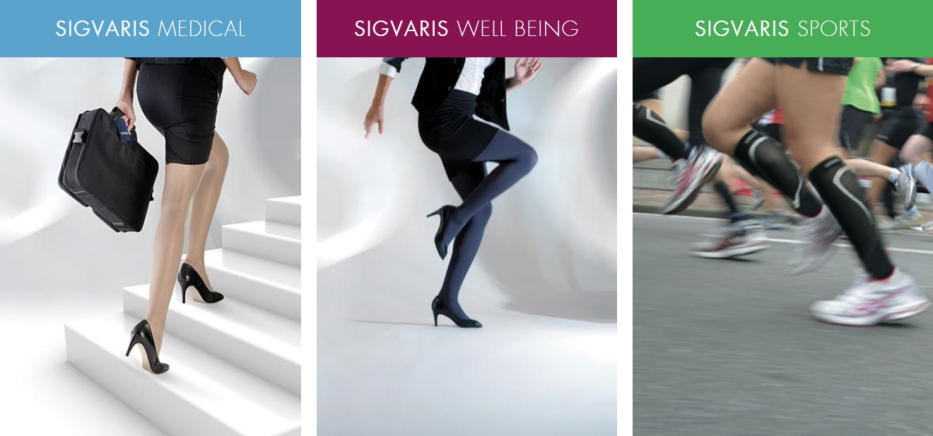

We Also Feature Support Products

Such As Arm, Knee & Back Supports

As Well As

Medical Support Stockings

Support Products

We Also Feature Support Products

Such As Arm, Knee & Back Supports

As Well As

Medical Support Stockings

Support Products

We Also Feature Support Products

Such As Arm, Knee & Back Supports

As Well As

Medical Support Stockings

Support Products